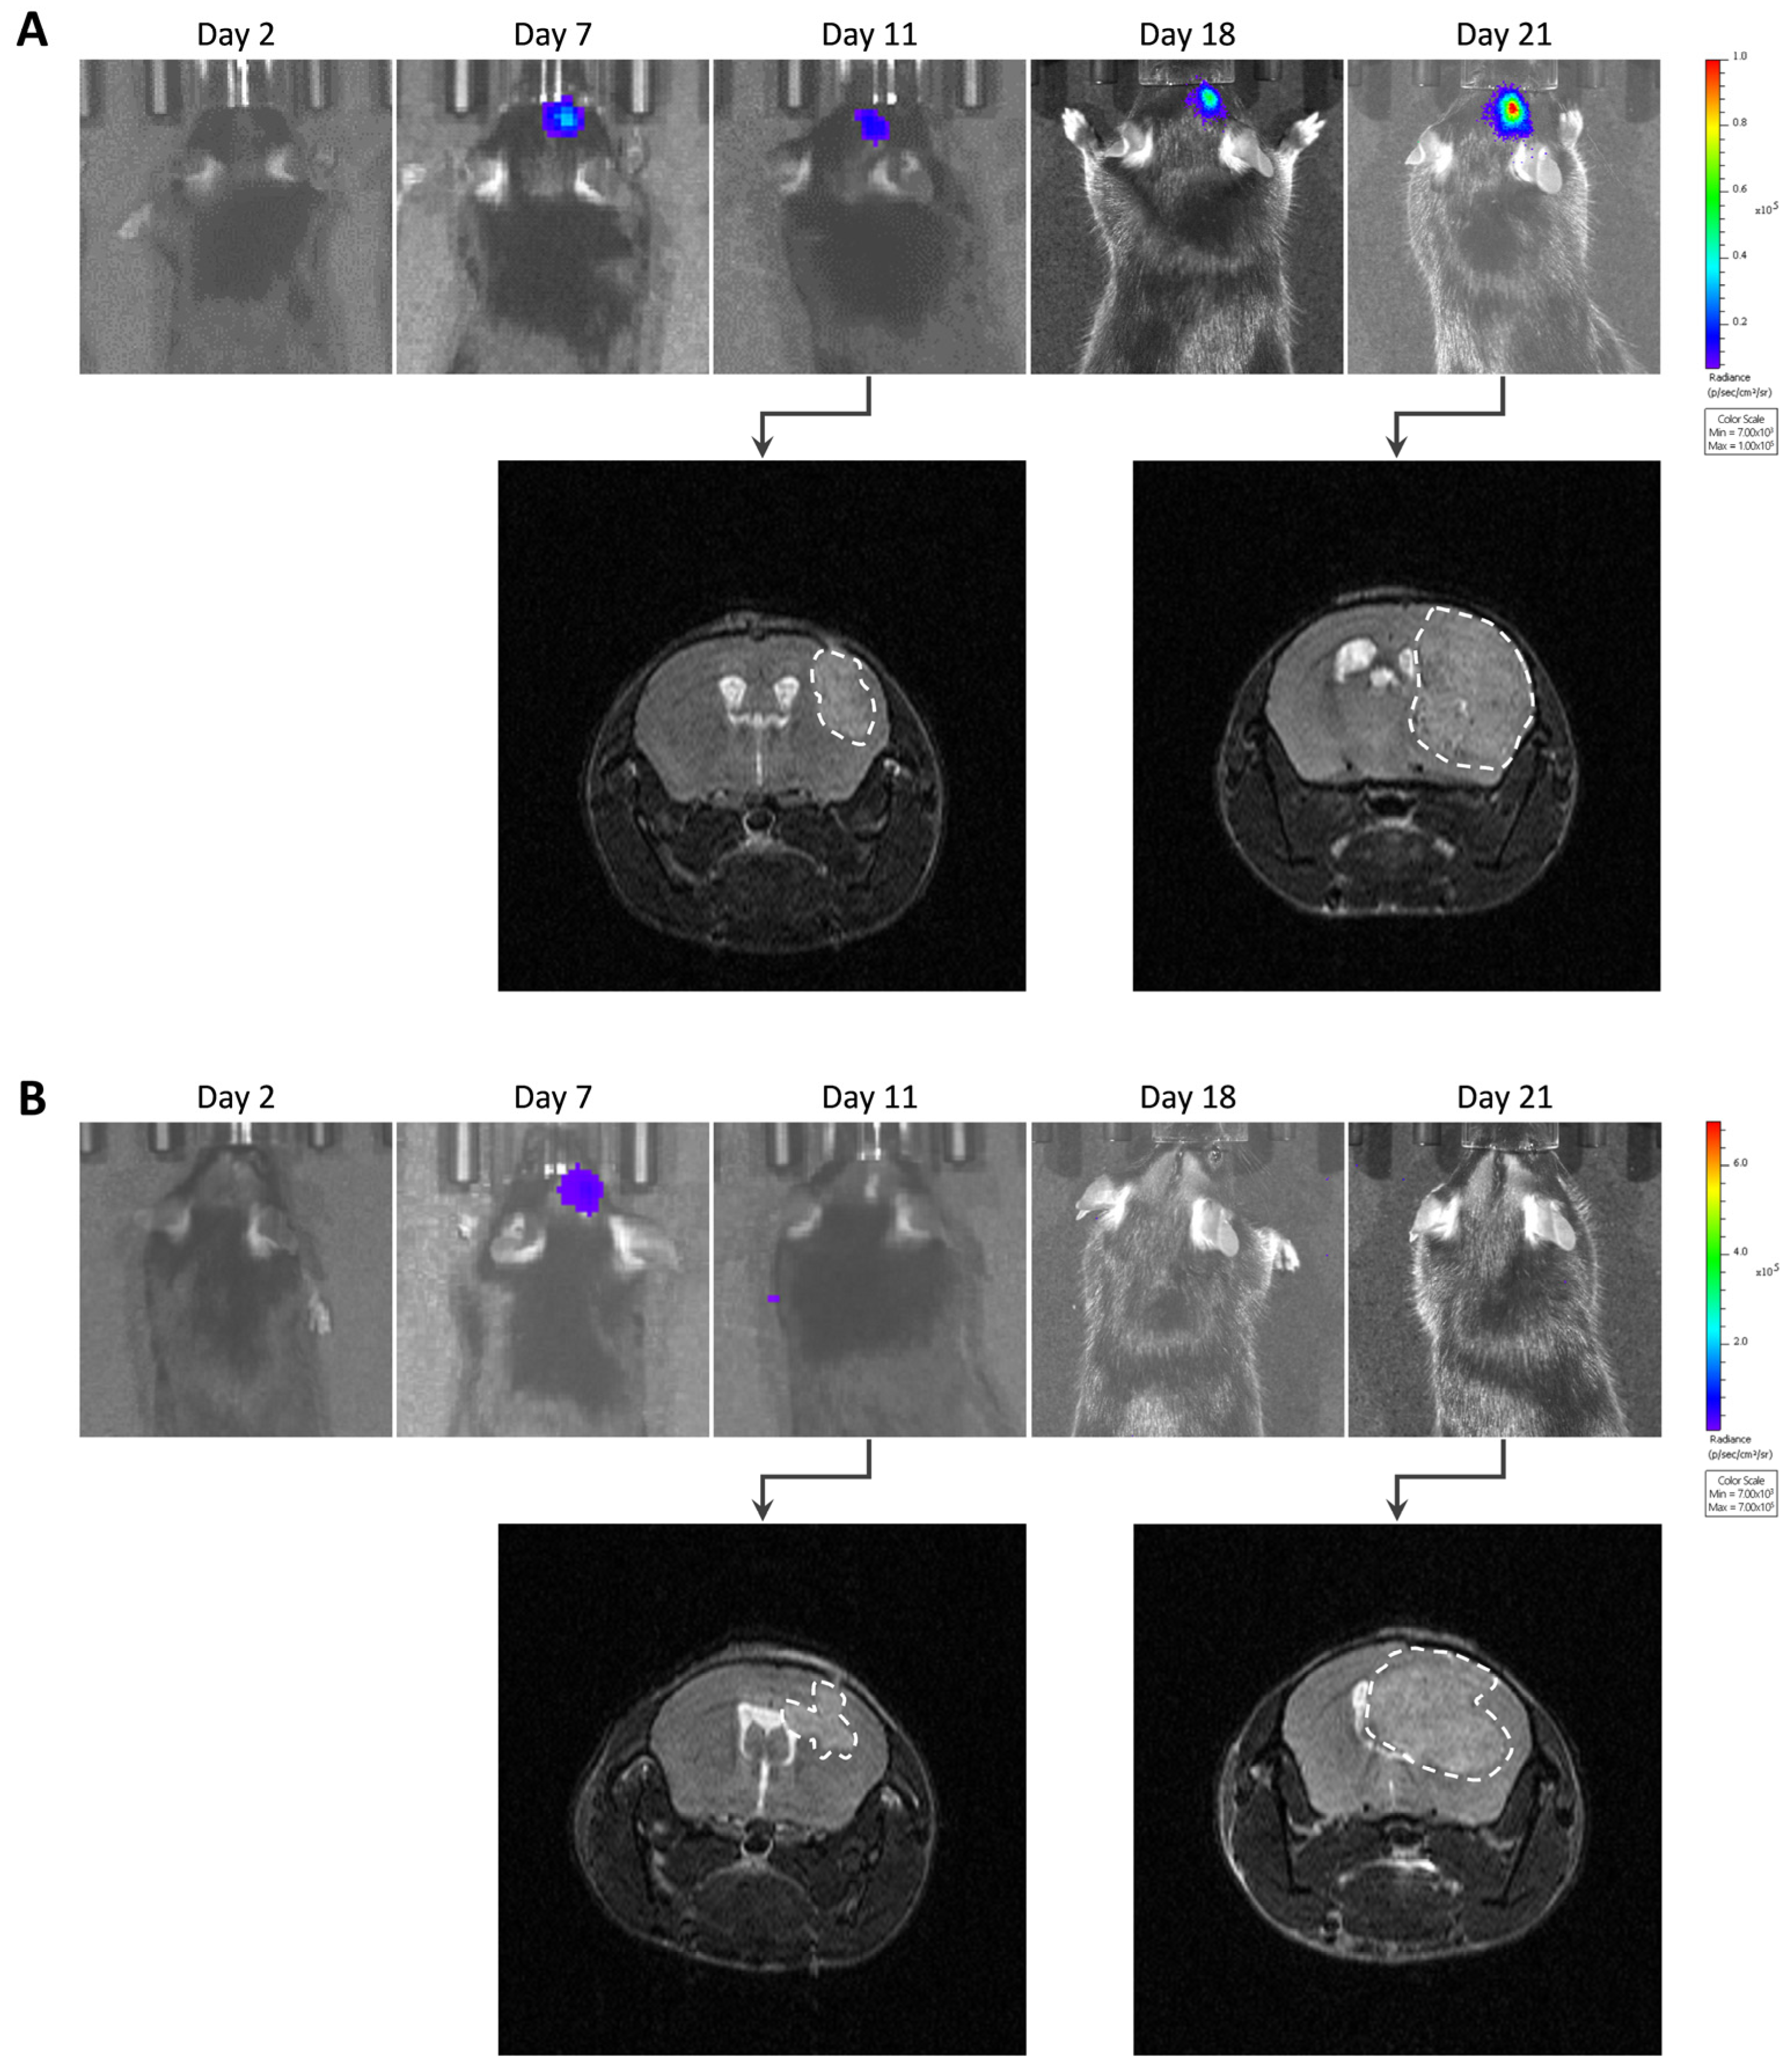

2.3. Tumor Imaging

2.3.1. Bioluminescence Imaging

2.3.2. Magnetic Resonance Imaging

3. Results